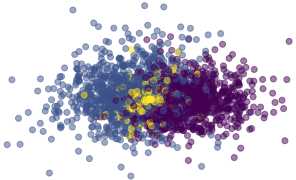

where the ReLU function forces the estimate of the KL divergence to be positive, thus avoiding to back-propagate wrong estimates of the density ratio due to the simultaneous training of . In (Abid & Zou, 2019), while Alg.1 of the original paper describes two distinct gradient updates, it is written that ”This discriminator is trained simultaneously with the encoder and decoder neural networks”. In practice, a single optimizer is used in their training code. In our work, we use an independent optimizer for , in order to ensure that the density ratio is well estimated. Furthermore, we freeze ’s parameters when minimizing the Mutual Information estimate. The pseudo-code is available in Alg. 1, and a visual explanation is shown in Fig.3.

Qualitatively, the model can be evaluated by looking at the full image reconstruction (common+salient factors) and by fixing the salient factors to for target images. Comparing full reconstructions with common-only reconstructions allows the user to interpret the patterns encoded in the salient factors (see Fig.1 and Fig.5).